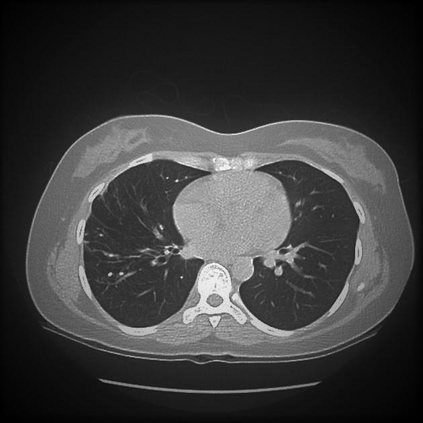

The evaluation of infectious disease processes on radiologic images is an important and challenging task in medical image analysis. Pulmonary infections can often be best imaged and evaluated through computed tomography (CT) scans, which are often not available in low-resource environments and difficult to obtain for critically ill patients. On the other hand, X-ray, a different type of imaging procedure, is inexpensive, often available at the bedside and more widely available, but offers a simpler, two dimensional image. We show that by relying on a model that learns to generate CT images from X-rays synthetically, we can improve the automatic disease classification accuracy and provide clinicians with a different look at the pulmonary disease process. Specifically, we investigate Tuberculosis (TB), a deadly bacterial infectious disease that predominantly affects the lungs, but also other organ systems. We show that relying on synthetically generated CT improves TB identification by 7.50% and distinguishes TB properties up to 12.16% better than the X-ray baseline.